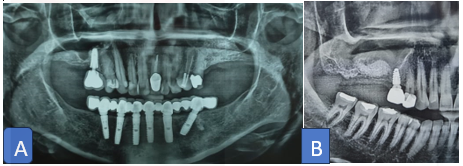

A resorbable collagen membrane was placed to close the lateral wall opening (figure 8), isolate the bone graft from the soft tissue flap and secure the bone graft in place. To prevent wound dehiscence, periosteum scoring was done to assure non-tension flap closure with double layer closure. The time of sinus lift procedures were estimated and ranged between 45-60 minutes. Postoperative instructions were given and medications were prescribed; patient was recalled after two weeks for suture removal. Post-operative radiograph was taken to evaluate the bone graft augmentation (figure 9).

All the cases treated with delayed implant placement or two-stage surgery. In delayed approaches, the healing period for the graft material ranged between 6 and 9 months. After bone graft healing period elapsed, implant placed following the manufacture standard and recommendation.

After three months, submerged implant exposed in second surgery then prosthetic part start to be initiated. All cases experience no major complications, bone graft intake was successful, decent implant stability (35Ncm and above). Patients followed up clinically and radiographically after loading with implant survival rate was 100%. The patient reported positive feedback when the posterior maxillary site was rehabilitated with sinus lift and implant placement, which restored function to the site

Figure 8: A resorbable membrane is fixed with sling sutures to close the lateral window opening

Figure 9: A &B, Postoperative radiograph (orthopantomogram) evaluates the sinus lift procedure and bone formation before implant placement